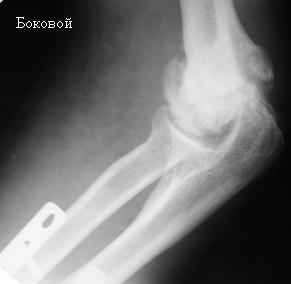

[Ortho] Стойкая комбинированная контрактура правого локтевого сустава

На консультации больной со стойкой комбинированной контрактурой правого локтевого сустава. В прошлом - спортсмен, сейчас охранник. Травма 2 августа 2008г., автодорожная. Оперирован в одной из больниц города. Остеосинтез, два месяца гипс. Объем движений с тех пор не изменился. Боли после физнагрузки (пытается тренироваться).

Хотелось-бы услышать мнения по объему оперативного лечения и послеоперационной реабилитации.